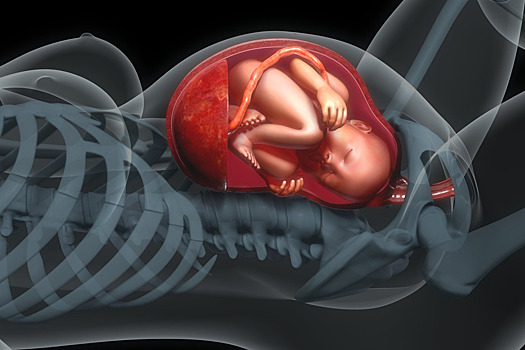

Российские медики нашли причину позднего токсикоза при беременности

Коллектив исследователей из ФГБУ «Национальный центр акушерства, гинекологии и перинатологии им. В.И. Кулакова» и ФГБУ «Национальный медицинский исследовательский центр сердечно-сосудистой хирургии им. А.Н. Бакулева» обнаружили в ворсинах плаценты необычный тип клеток — телоциты. Как правило, они встречаются на границе нервной и мышечной тканей, однако в плаценте нет нервов. Роль телоцитов в ворсинах плаценты пока до конца не ясна, но есть предположение, что нарушение их нормального функционирования существенно повышает риск опасного для будущей матери и плода состояния — преэклампсии (позднего токсикоза). Научная статья опубликована в журнале Scientific Reports. Телоциты — тип клеток, открытый совсем недавно. Их длинные ветвящиеся на концах отростки, как правило, примыкают к клеткам гладких мышц в стенках сосудов или к клеткам тонкого кишечника. Они способны задавать ритм гладким мышцам, благодаря чему последние сокращаются с определенной частотой. Также телоциты, вероятно, выполняют ряд иммунных функций. Несмотря на то, что нервных клеток в плаценте не обнаружено, ученые попытались обнаружить телоциты в структуре ткани плацентарных ворсин — выростов, погруженных в небольшую полость, заполненную материнской кровью и поглощающих из нее питательные вещества. Во время операций по кесаревому сечению они собрали образцы плацентарных ворсин у 37 женщин, чья беременность протекала нормально, и у 15 рожениц, перенесших преэклампсию в различных формах. Ворсины нарезали на тонкие слои ткани и поместили в жидкость, содержащую флуоресцентные красители. Они «светились» лишь в том случае, когда на поверхности клеток присутствовали молекулы, характерные для телоцитов. Дополнительный набор красителей с тем же принципом действия помог определить, какие молекулы, характерные для клеток иммунной системы, эти телоциты выделяют. Также часть препаратов рассмотрели при большем увеличении с помощью электронного микроскопа. Выяснилось, что телоциты в ворсинах плаценты видели и ранее, но ошибочно относили их к другим типам клеток. Плацентарные телоциты разделили на несколько групп по тому, какие молекулы в них присутствуют. Наиболее важный для медицины вывод — ворсины плацент беременных, перенесших преэклампсию, содержат существенно меньше белка TMEM16a — а значит, и самих телоцитов. Дело в том, что TMEM16a присутствует во всех телоцитах и во многом обеспечивает их функцию как водителей ритма. Когда работу этого белка блокируют в телоцитах кишечника, движения его гладких мышц, проталкивающих вперед комки полупереваренной пищи, ослабевают. В сосудах ворсин плаценты при преэклампсии, по-видимому, происходит похожий процесс, за счет чего кровообращение матери и плода нарушается. Преэклампсия (поздний токсикоз беременности) — это патологическое состояние будущей матери, которое характеризуется повышенным артериальным давлением и появлением в моче заметных количеств белка (в норме его там быть не должно), разрушением клеток крови, а также нарушением функций печени и почек. Оно проявляется на сроке 20 недель и позднее и существенно повышает вероятность осложнений последующего течения беременности и родов. При отсутствии лечения преэклампсия может перейти в эклампсию — состояние, угрожающее жизни беременной и плода. Причины преэклампсии пока не установлены, и тем важнее выявить их.